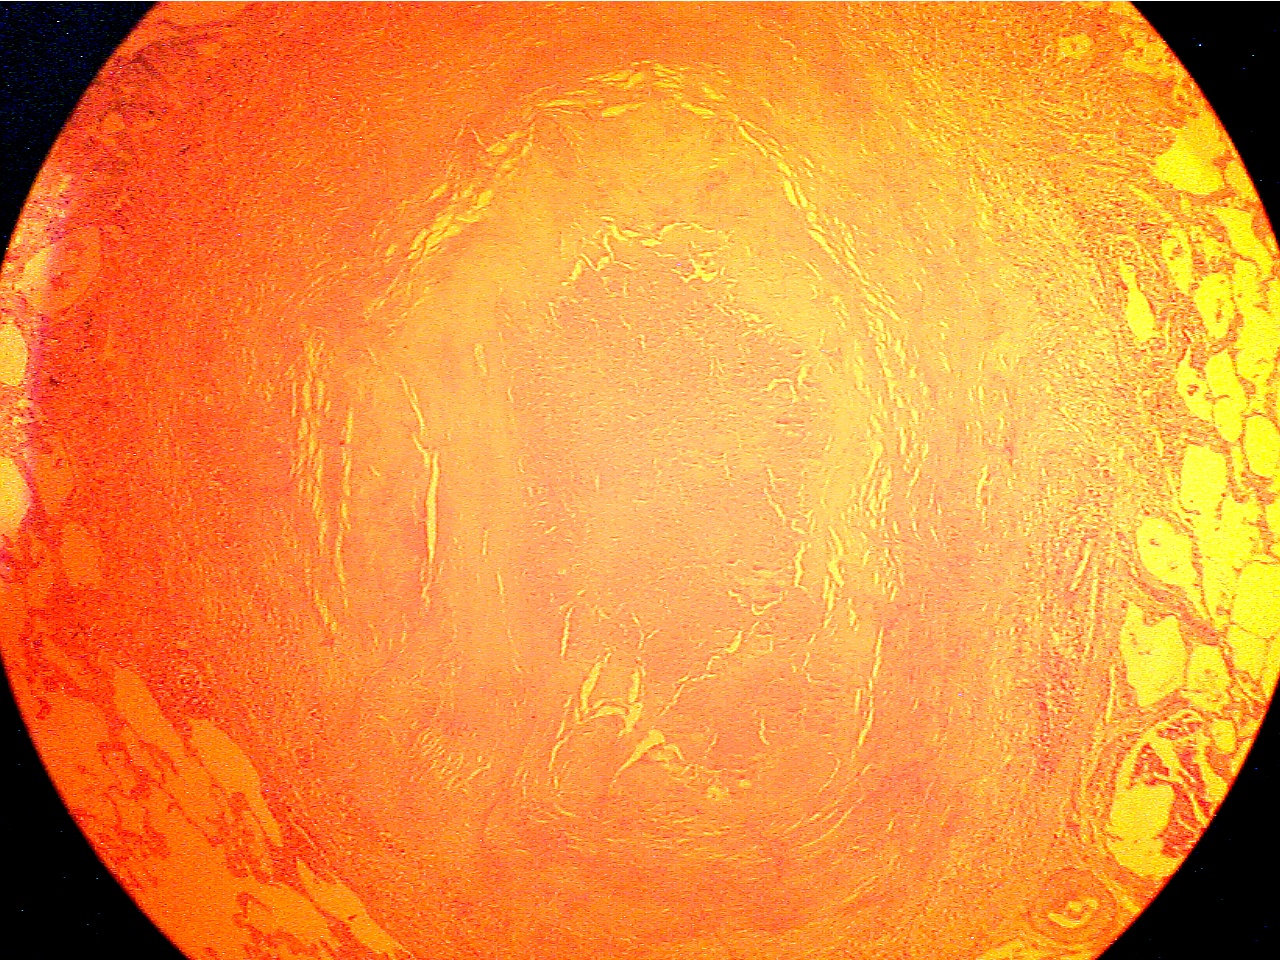

Ghon tubercle - entire (40X1.0)

Ghon tubercle (40X2.0)

Tubercle in center with necrotic core surrounded

by Normal lung (lower

left), capsule (granular and fibrous

capsule, normal lung on extreme left and

right

layers), and core of necrotic material

(center to right edge)